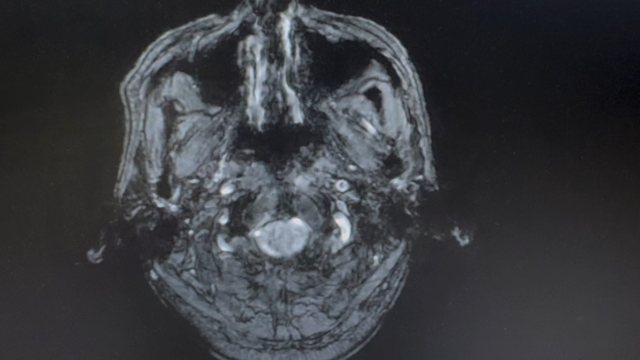

【神经】特别精彩病例|男,55岁,不明病因中度甲状腺功能减退1年

病例信息【患者信息】:男,55岁【现病史及既往史】:不明病因中度甲状腺功能减退1年【检查】: